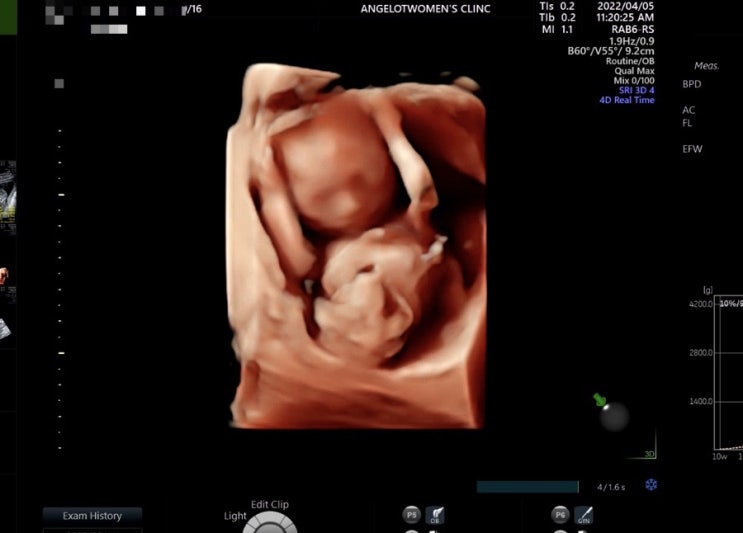

임신 24주 25주 배크기, 아랫배 땡김, 임산부 복대, 아기용품 구입, 임당검사

24주 7개월 진입 벌써 7개월이라니... 임신 중기 막바지라니.... 배 볼록- ㅎㅎ 다들 배 안나왔다고 놀래는...

임신 22주 23주 배크기, 정밀초음파, 임신 중기 소화불량 메스꺼움, 태동, 임산부 만보걷기

22주 진입 22주 배크기 진짜 배가 안나오는 것 같다 아기는 주수대로 잘 크고 있으니 걱정 안해도 되겠지? ...